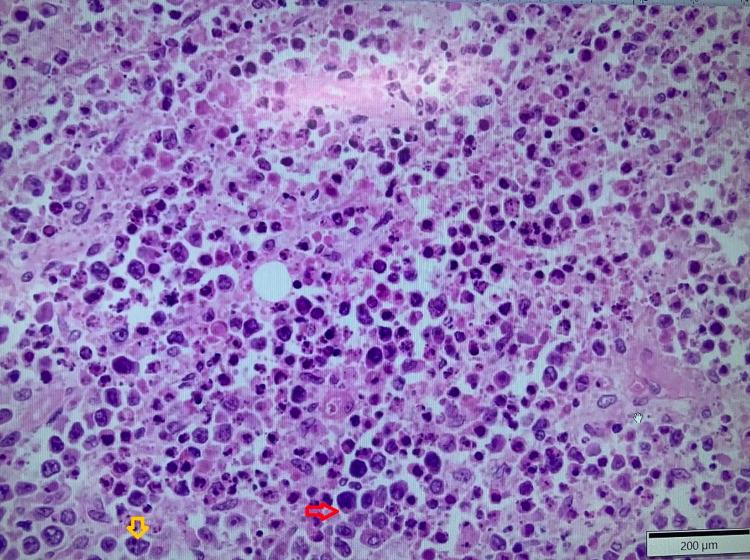

A Patient With Regressed Diffuse Large B-Cell Lymphoma and Aggressive Follicular Lymphoma.

Diffuse large B-cell lymphoma (DLBCL) and follicular lymphoma (FL) are the two most aggressive forms of non-Hodgkin lymphomas (NHLs). Spontaneous remission of DLBCL is a rare phenomenon. Immune system activation has been observed to play a significant role in the regression of untreated disease on some occasions. We present a case of DLBCL in a 75-year-old male patient who has been free of disease for two months without any treatment due to possible immune-related mechanism, but later he presented with FL.